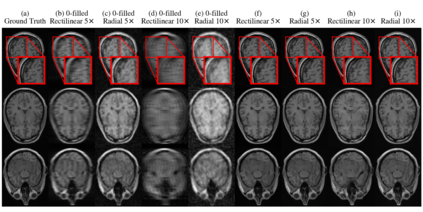

In spite of its extensive adaptation in almost every medical diagnostic and examinatorial application, Magnetic Resonance Imaging (MRI) is still a slow imaging modality which limits its use for dynamic imaging. In recent years, Parallel Imaging (PI) and Compressed Sensing (CS) have been utilised to accelerate the MRI acquisition. In clinical settings, subsampling the k-space measurements during scanning time using Cartesian trajectories, such as rectilinear sampling, is currently the most conventional CS approach applied which, however, is prone to producing aliased reconstructions. With the advent of the involvement of Deep Learning (DL) in accelerating the MRI, reconstructing faithful images from subsampled data became increasingly promising. Retrospectively applying a subsampling mask onto the k-space data is a way of simulating the accelerated acquisition of k-space data in real clinical setting. In this paper we compare and provide a review for the effect of applying either rectilinear or radial retrospective subsampling on the quality of the reconstructions outputted by trained deep neural networks. With the same choice of hyper-parameters, we train and evaluate two distinct Recurrent Inference Machines (RIMs), one for each type of subsampling. The qualitative and quantitative results of our experiments indicate that the model trained on data with radial subsampling attains higher performance and learns to estimate reconstructions with higher fidelity paving the way for other DL approaches to involve radial subsampling.